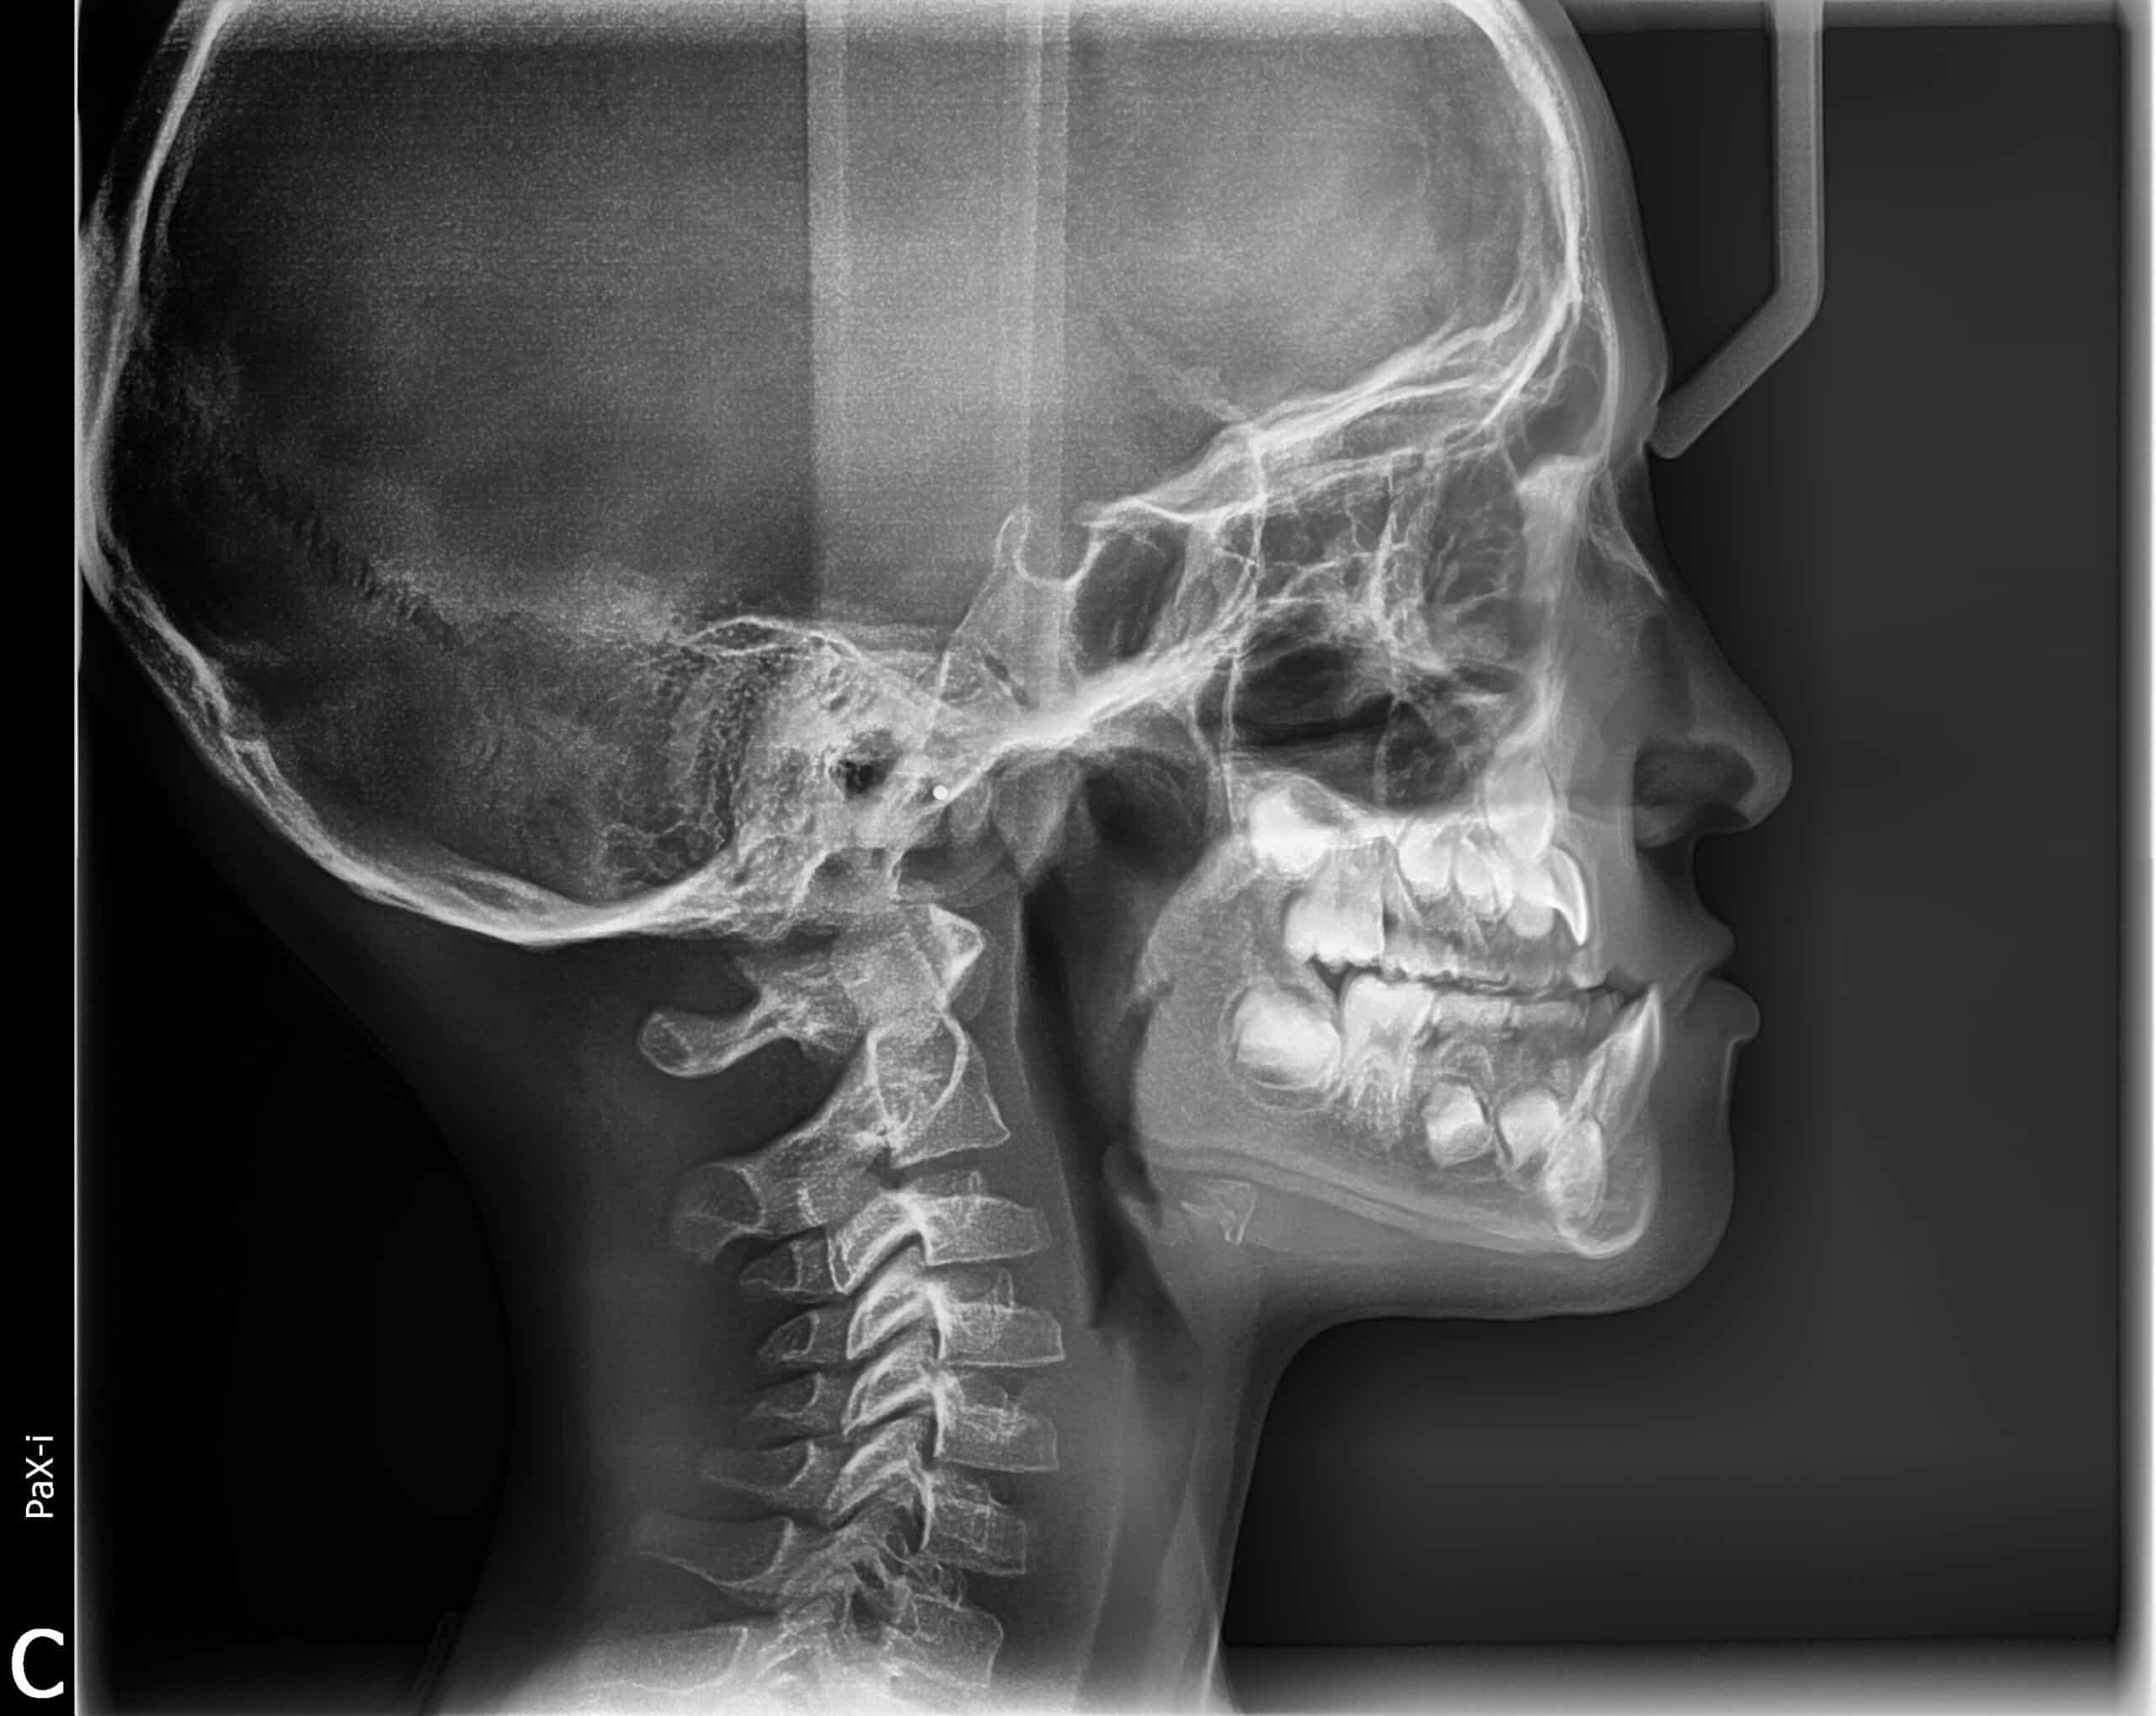

Case Study: Early Underbite Treatment in Kids

Avoid Extensive Treatment Later in Life

Early orthodontic evaluations can play an important role in identifying and addressing developing bite concerns in children. In this case, a young patient was first monitored at age 7 and began treatment at age 8 to correct a developing underbite. By guiding jaw growth at the right stage of development, early intervention helped correct the bite and reduce the likelihood of more complex treatment later.